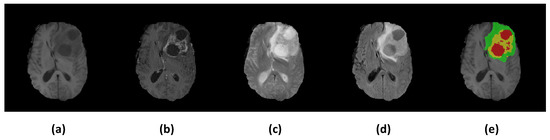

3.1. Dataset